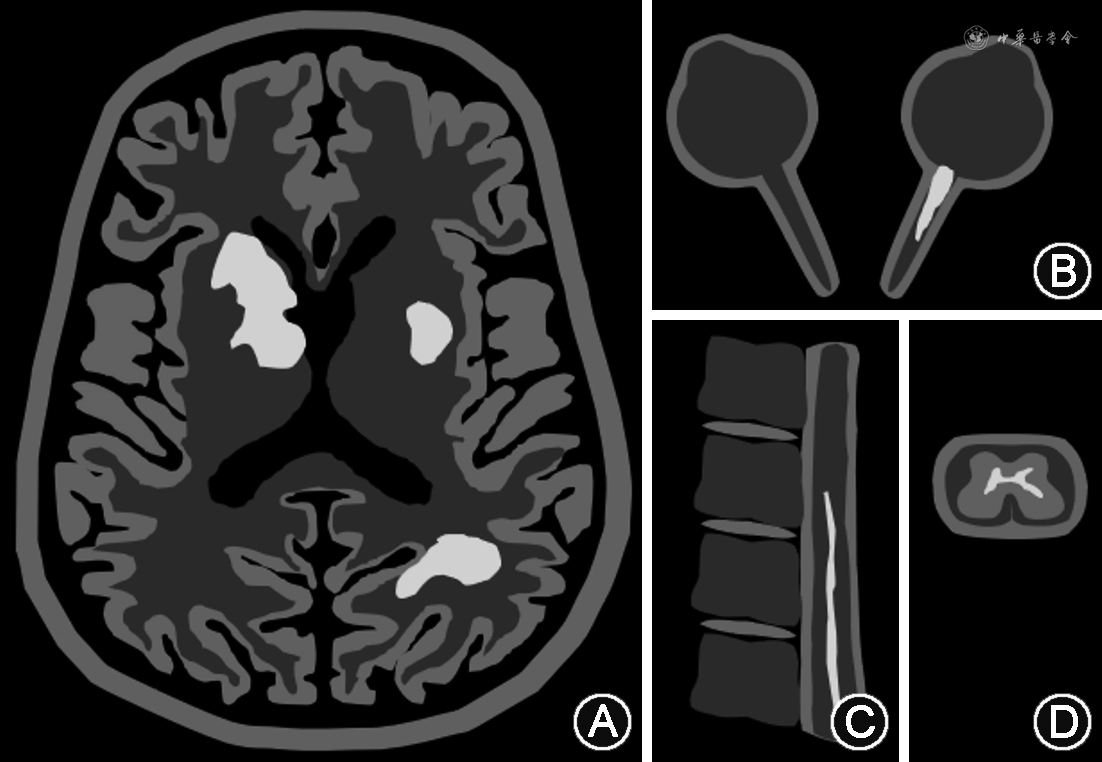

根据中国专家组建议的MOGAD诊断标准[21],如在疑似人群中应用规范LCBA检测方法检出血清抗人全长MOG-IgG1阳性,且不存在MOGAD的诊断“红旗征”,即已排除其他可能的诊断,则诊断可以成立(图2)。

MOGAD:髓鞘少突胶质细胞糖蛋白抗体相关疾病;LCBA:活细胞法的抗体检测;MOG:髓鞘少突胶质细胞糖蛋白